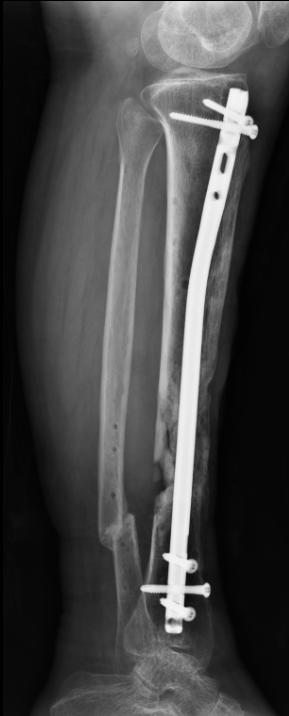

于阿姨看到了治疗的希望,虽仍受病痛折磨但脸上已经渐渐恢复了笑容。接下来要攻破的难关就是对于长达10cm的骨质缺损如何进行重建。骨三科团队共同探讨研究后决定采用了Masquelet技术重建10cm的骨缺损。2023年5月,第二次手术如期进行,拆除VSD负压吸引装置,清创后对胫骨进行髓内针内固定,骨缺损部位采用骨水泥填充占位,皮瓣移植覆盖缺损皮肤。2023年7月,于阿姨迎来了第三次手术,为促进骨折愈合这次手术进行了取双侧髂骨结合人工骨植骨,手术过程非常顺利。